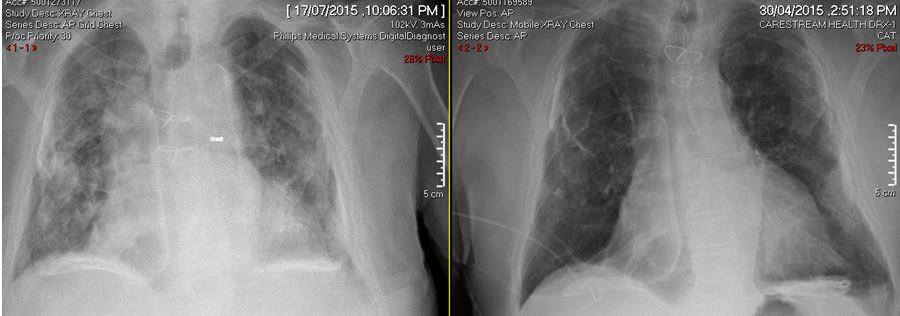

Severe pneumonia due to metapneumovirus in an 80 year old male from an RACF